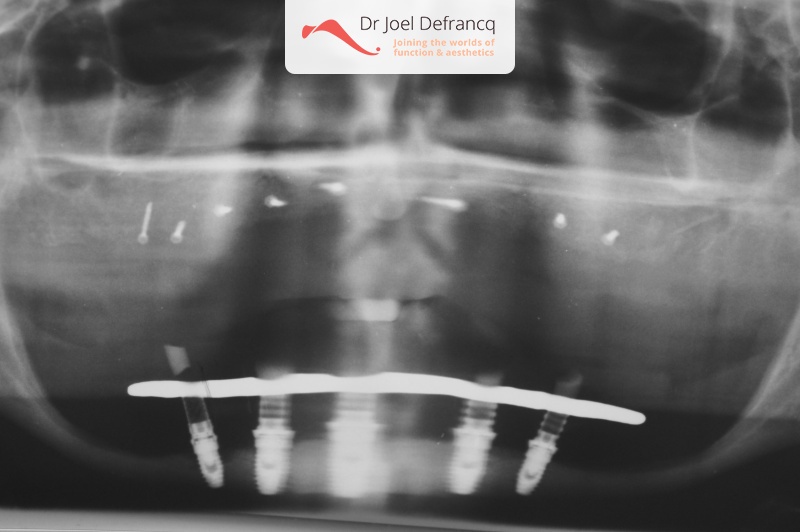

Daphne: from extreme atrophic to fixed teeth on implants

Behandeling tandheelkundige implantaten

- Vaste tanden op implantaten (onderkaak)

- Implantaten met beenopbouw